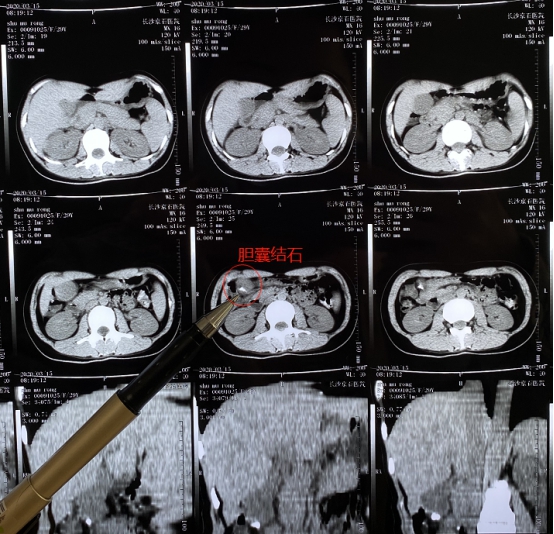

(患者腹部CT局部图)

3月14日 , 入院后经CT检查 , 舒女士被确诊为胆结石并发慢性胆囊炎 。 住院后 , 医生考虑到舒女士想保胆并且不想留疤的需求 , 结合舒女士病情 , 长沙京石结石医院肝胆结石科专家团队为其施行了经脐无痕超微创保胆取石术 , 仅在肚脐眼打一个小孔 , 就可置入特殊内镜取石 。 手术成功取出患者体内十多颗黄豆大小的结石 , 并且保留了有功能的胆囊 。